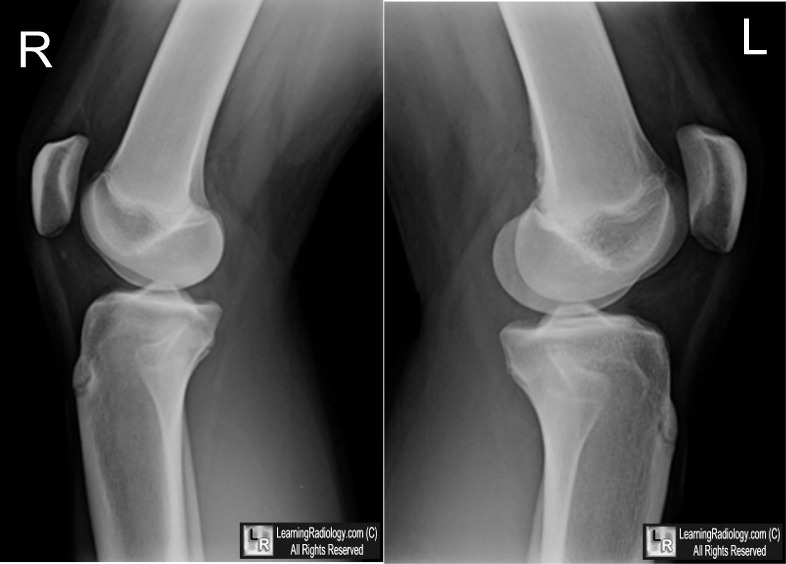

Cortical Desmoid. Note the cortical irregularity of the distal, posterior femur on the left side (yellow arrow) with no associated bone destruction or soft tissue mass. Although frequently bilateral, the right knee in this patient is normal (white arrow) and demonstrates the normal appearance of the cortex.

For this same photo with the arrows, click here